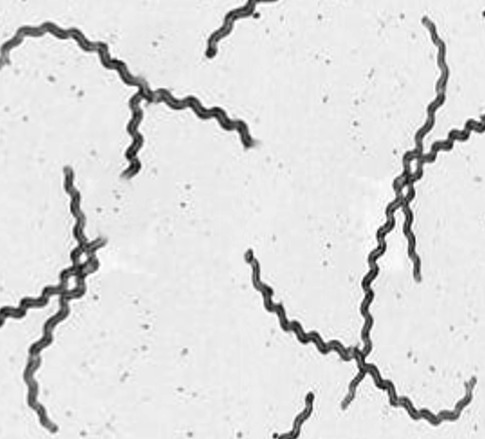

这个所谓“鼠尿病”就是钩端螺旋体病,虽然这个词语再健康传播领域使用频率很高,经常被政府公共卫生部门和媒体用来进行健康宣教[1],但是说实话这个词用词并不准确,钩端螺旋体病(以下简称“钩体病”)并不仅依靠沾染鼠尿传播,甚至钩体病都未必与家鼠有关。 钩体病是由致病性钩端螺旋体(Leptospira)所致的急性动物源性全身感染病。钩体属于螺旋菌目(Spirochaetales)的钩端螺旋体科。螺旋体是一类革兰氏阴性、有动力的微生物,其突出特点就是菌体呈真正的螺旋形,而非弧状或弯曲状,类似于一个微型弹簧,螺旋体的运动方式可以是像钻头一样沿菌体纵轴旋转前进,也可以像弹簧一样在液体中伸缩前进,还可以像蛇一样匍匐爬行[2]。 |

暗视野显微镜下的钩端螺旋体,注意其弯曲成钩状(https://www.ncbi.nlm.nih.gov/books/NBK441858/figure/article-24195.image.f1/) 钩端螺旋体和其他螺旋体最大的区别就是其菌体会自然弯曲成“钩”,类似于一个被掰弯的螺丝钉。这让它与其他致病性螺旋体(比如梅毒的病原体――密螺旋体)在显微镜下容易区分。 |